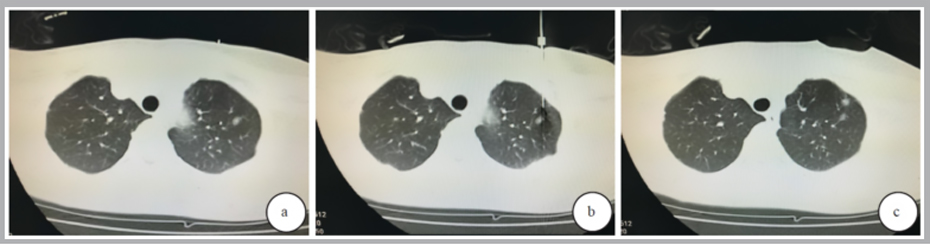

图例:穿刺前后 CT 图像

a:穿刺前; b: 图2 穿刺中,距离病灶5 mm 处注射医用胶;c: 穿刺后,医用胶注射后形成质地坚硬的胶粒。